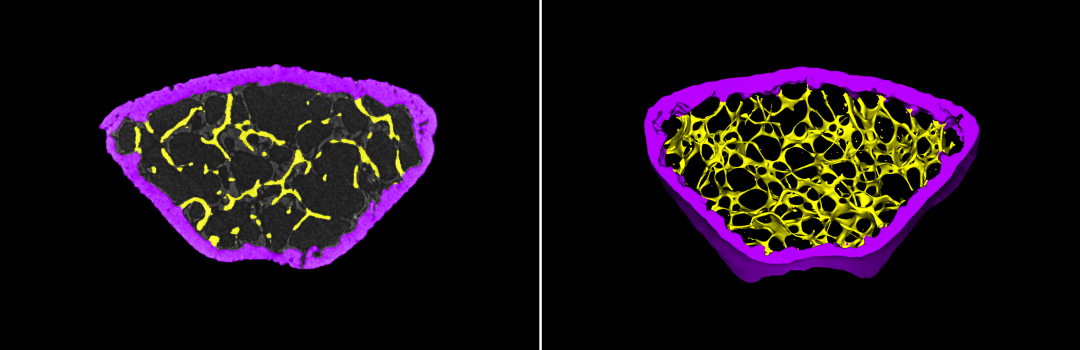

2D及3D骨小梁和皮质骨分割提取

案例说明:在大鼠头部去除骨膜以暴露顶骨,建立直径为5毫米的缺损模型,将仿生骨膜放置在缺损处,八周后使用锐视科技Micro-CT成像系统IMAGING 100对大鼠的颅骨扫描成像,评估缺损区域的新骨形成情况。可观察到使用骨生成材料的治疗组大鼠颅骨(右图)恢复情况好于对照侧(左图)。